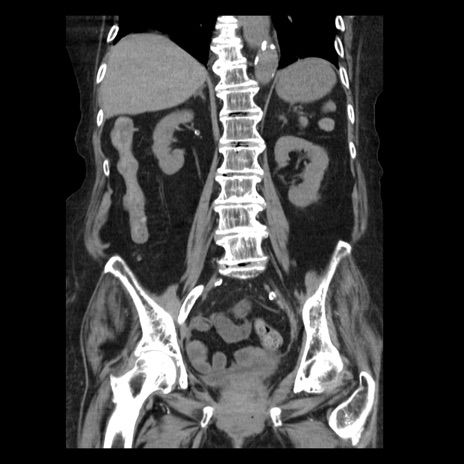

横断像

症例14(冠状断像)

【症例】 90歳代女性

【主訴】 腹痛・嘔吐

【現病歴】今朝から左側腹部痛を認めた。 経過観察していたが、嘔吐を認めたため来院。

【既往歴】 子宮癌術後

【身体所見】 意識清明、BP 127/54mmHg、P 98bpm Sp02 95%(RA)、BT 35.8°C、腹部平坦・軟腸ぜん動音聴取良好、右下腹部圧痛(+) 反跳痛なし

【データ】WBC 9800、CRP 0.46